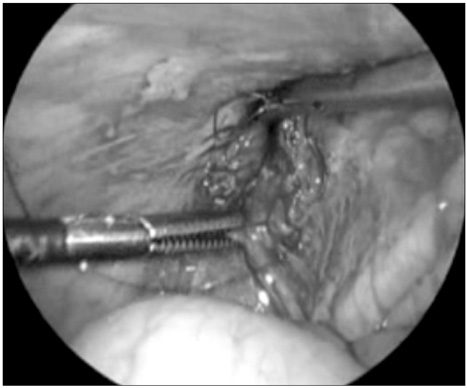

Fig. 2

The purse-string suture with non-absorbable suture.

Fig. 2 The purse-string suture with non-absorbable suture.